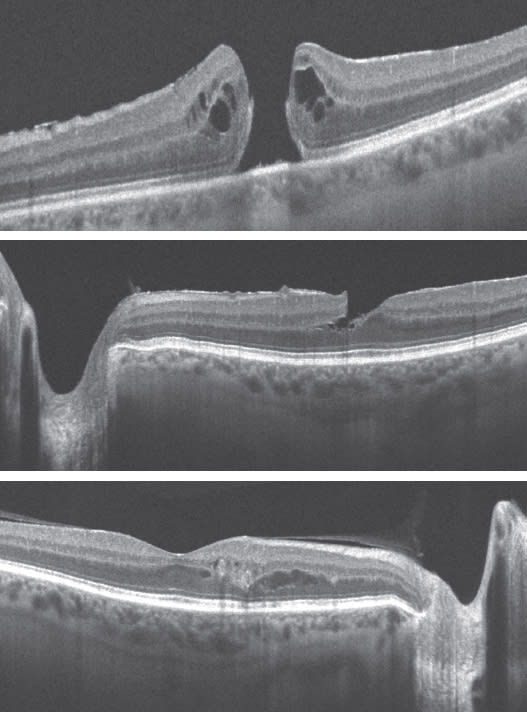

The more common conditions the cataract surgeon should be concerned about are vitreomacular traction syndrome and epiretinal membranes (ERMs), whether they are visually significant or not, because after cataract surgery, the vitreous may partially separate and cause more traction, and the ERM can become visually significant. That is not to say, however, that a premium IOL would be contraindicated in the presence of a minor epiretinal membrane because most are not visually significant, but certainly it should be documented preoperatively. These membranes can be quite subtle, but with Cirrus SD-OCT B-scan (Figure 1) and C-scan, diagnosis is simple. The cataract surgeon may decide to send the scan to the retina specialist to determine whether or not the ERM is visually significant, and to discuss which type of IOL should be implanted, and if the macular problem should be addressed before or after the cataract surgery.

Figure 1. Determining if an epiretinal membrane is present before cataract surgery is an important step in patient management and can be done easily with Cirrus HD-OCT.